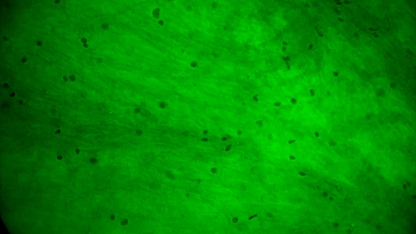

术中EndoSCell®细胞图像如下:

2.手术切缘处发现的正常脑白质:细胞核形态正常,密度低且分布均匀。